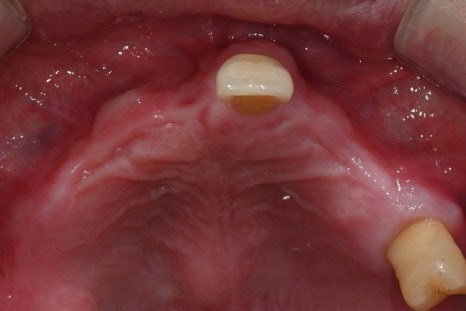

· 상악은 잇몸뼈가 매우 얇고 치아가 거의 남아 있지 않은 상태

치료 계획 및 수술 과정

이 환자분은 다음과 같은 계획으로

치료를 진행했습니다.

· 수면마취(의식하 진정요법) 하에 진행

· 상악 양측 상악동 거상술 + 임플란트 10개 식립

· 하악 발치 후 결손 부위 포함 임플란트 6개 식립

임시치아부터 최종 보철까지의 과정

수술 직후에는

임시틀니 대신 고정형 임시치아를 적용하여

일상생활과 식사 불편을 최대한 줄였습니다.

· 수술 다음 날 임시치아 장착

· 하악 일부는 2개월 내 조기 보철 완성

· 상악은 뼈이식 안정화를 충분히 거쳐 진행